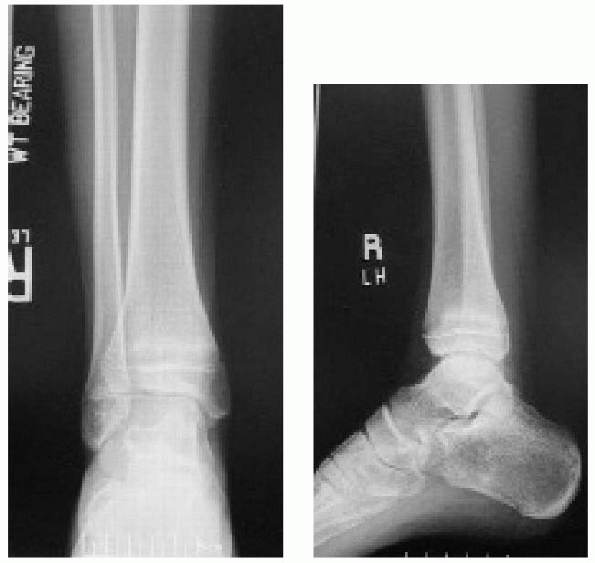

![]() |

|

FIGURE 26-10 A. Anteroposterior radiograph of Salter Harris type III/juvenile Tillaux Fracture. B. Lateral radiograph of Salter Harris type III/juvenile Tillaux Fracture.

III fracture involving the anterolateral distal tibia. The portion of

the physis not involved in the fracture is closed (Fig. 26-10).

FIGURE 26-11 A. Anteroposterior view of triplane fracture. On this view, the fracture appears to be a Salter-Harris type III configuration. B. Lateral view of triplane fracture. On this view, the fracture appears to be a Salter-Harris type II configuration. C. Three-dimensional CT reconstruction can demonstrate significant metaphyseal displacement. D. Three-dimensional CT reconstruction can demonstrate intra-articular displacement.

common the appearance of a Salter-Harris type III fracture on the

anteroposterior radiographs and of a Salter-Harris type II fracture on

the lateral radiographs (Fig. 26-11). CT scans can be very helpful to understand the complex anatomy of these fractures (see Fig. 26-11). It has been proposed that the mechanism of injury for Tillaux and triplane fractures is external rotation.47,148